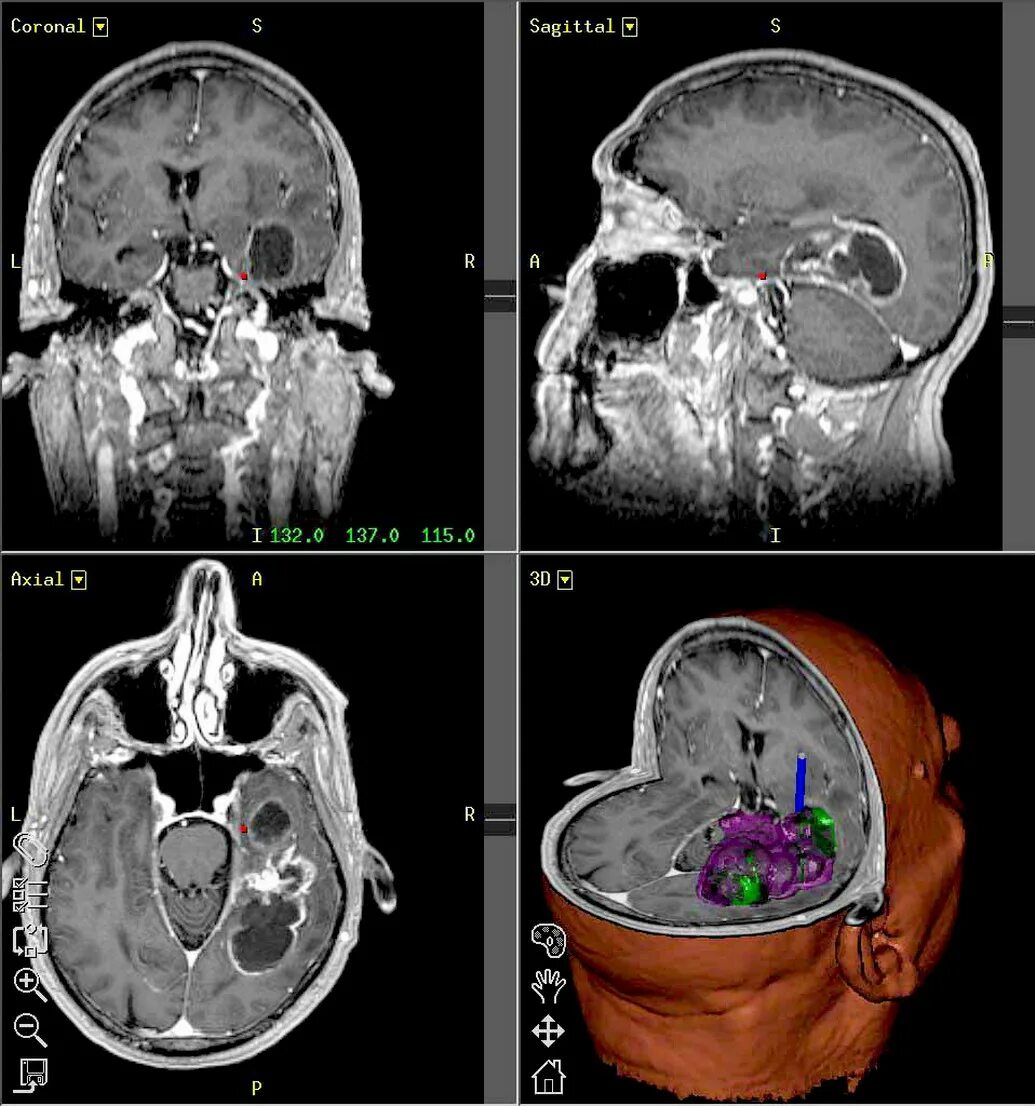

Мрт симптомы